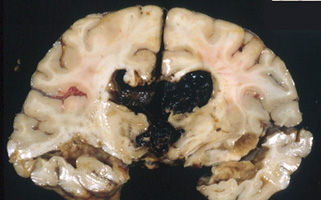

Question 19: The lesion illustrated below is due primarily to vascular occlusion

True. The lesion is a hemorrhagic infarct in the distribution of the RMCA.

The basic mechanism is arterial occlusion, usually by an embolus, with reperfusion and leakage

through a damaged capillary bed following lysis of the embolus.

False. The lesion is a hemorrhagic infarct in the distribution of the RMCA.